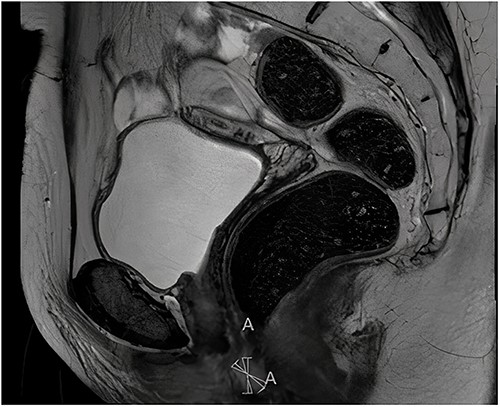

After 1 month of initial diagnosis, an excision of the tumour was performed through open approach with primary closure of the vaginal wall. Histopathological examination confirmed the solid tumour to be metastatic disease from rectal origin with free margins. The newly discovered symptoms related to the rectovaginal septum metastasis had completely disappeared following the excision. Upon further follow-up at 2 years and 6 months; routine lab results showed a significant increase in the CEA levels at 5.2 ug/l (3 months prior at 4.0 ug/l). Given this significant increase; a PET-scan was again performed. The PET-scan revealed a lesion within the left lower lobe of 5.7 cm in a transverse plane; suspected to be distant metastasis (see Fig. 3). Compared to the last PET-scan, this lesion was a new development not previously seen. CT-guided thoracic biopsy confirmed by histopathological examination, that this lesion was indeed a distant metastasis of the previous rectal cancer.

Transverse- and sagittal plane of the PET-scan showing a leasion in the left lower lobe with metabolic activity.